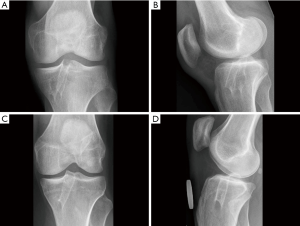

At the 5-year follow-up, there was no significant difference in the rotational stability of the knee anymore. However, the patients with the single-bundle ACL reconstruction had significantly more graft failures leading to the revision ACL surgery than the patients with the double-bundle technique. At 5 years, the x-rays showed no significant differences at osteoarthritic rates between the patients with the single-bundle and the double-bundle procedures (25). The MRI evaluation in the patients with the double-bundle ACL reconstruction showed that the tunnel enlargement seen at 2 years was followed by tunnel narrowing at 5-year follow-up. Tunnel ossification resulted in evenly narrowed tunnels in 44%, in conical tunnels in 48%, and fully ossified in 8%. At 5 years, none of the bioabsorbable screws was anymore completely visible, and 19% of them were already fully ossified (Figure 3) (39).

At the 10-year follow-up, the double-bundle technique resulted in significantly fewer graft failures than the single-bundle ACL reconstruction during the follow-up. Knee stability and osteoarthritic rates were similar at 10 years (Figure 4) (19).